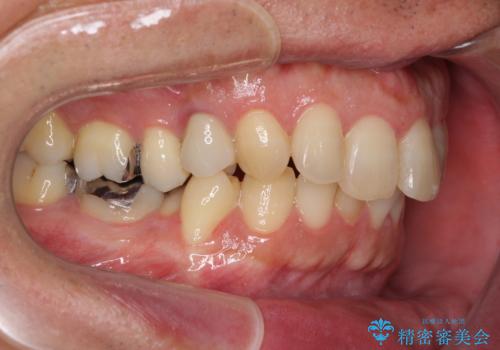

- 外に飛び出した側方の歯と、前歯のデコボコを気にして来院された患者様です。

IPR(歯と歯の間を削る)によってデコボコが解消するように設計し、インビザラインにより治療を行うこととしました。

治療途中で1年半以上通院されない時期があったため、後戻りが生じたことで治療期間が長くなってしまいました。

親知らずを抜去したことで、下顎のデコボコがきれいに解消されました。